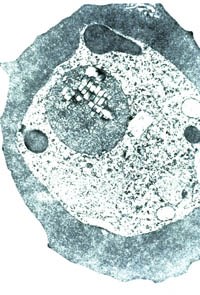

Ký sinh trùng sốt rét (KSTSR) nằm trong hồng cầu người, trong có không bào và thành phần heme có thể thấy được. Dựa vào cơ chế này, những nhà nghiên cứu Đại học Washington đã khám phá ra một phương pháp điều trị sốt rét áp dụng lĩnh vực từ tính, điều này có thể mở ra một cuộc cách mạng chống SR- mà trước nay Tổ chức Y tế thế giới gọi là phức hợp sức khoẻ phức tạp và đáng quan tâm.

Giáo sư sinh học Henri Lai, một nghiên cứu viên của Đại học Washington nói rằng KSTSR plasmodium có thể lu mờ hoặc chết khi cho chúng tiếp xúc với từ xoay (oscillating magnetic), điều này làm cho những phần tử chứa ion sắt bên trong có KSTSR chuyển động theo hướng phá huỷ KSTSR. Trong hai thập niên qua, sự cảnh báo về KSTSR kháng thuốc là một vấn đề nan giải trong công tác phòng chống sốt rét, phương pháp điều trị này có thể là cầu nối vì KSTSR không thể kháng theo cơ chế từ tính này. Vì KSTSR ăn Hb trong hồng cầu của vật chủ. Chúng ăn phần globin của phân tử Hb, nhưng phần sắt hay Hem vẫn còn nguyên vẹn vì KSTSR thiếu enzyme phân huỷ nó. Điều này dẫn đến một vấn đề cho KSTSR bởi vì những phần tử hem tự do có thể gây ra một chuỗi oxy hoá acide béo không bảo hoà, đưa đến phá huỷ màng KST. KSTSR tan rã.